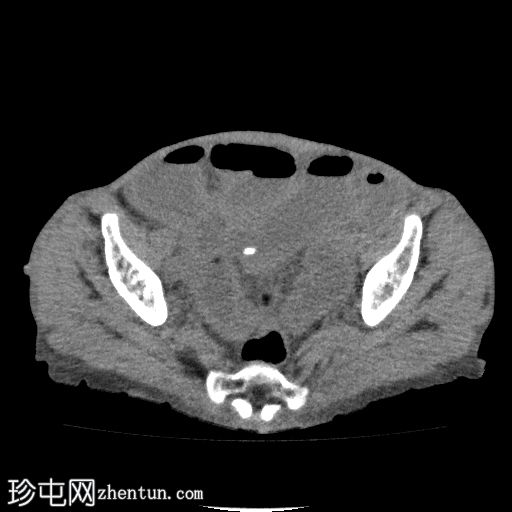

CT

轴位

平扫

回肠肠袢套入盲肠,形成肠套叠形态,轴位和纵位图像分别可见靶征和腊肠征或假肾征。